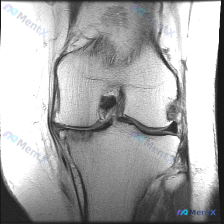

初看以为是软骨异常,读片后发现核心问题出在这?

刚看到一张有意思的膝关节MRI读片病例,整理出来分享下思路。

病例影像资料

提供的是膝关节MRI-T1加权序列冠状位图像,分析可见:

- 骨骼结构:股骨远端、胫骨近端皮质连续,无明显骨折或骨质破坏;T1序列骨髓信号为弥漫中等信号,无明显异常低/高信号

- 半月板:内、外侧半月板形态信号均正常,内侧呈典型领结状低信号,外侧信号均匀

- 关键异常:位于关节中央髁间窝的前交叉韧带(ACL)走行区,可见结构紊乱、信号不均匀,韧带连续性显示不清,这是本次影像最突出的发现

- 关节间隙:间隙宽度尚可,无明显关节软骨极度变薄或剥脱

- 侧副韧带:内、外侧副韧带走行清晰,信号无明显异常,无连续性中断

- 其他:关节囊周围软组织、肌肉间隙无明显异常肿块或局限性积液